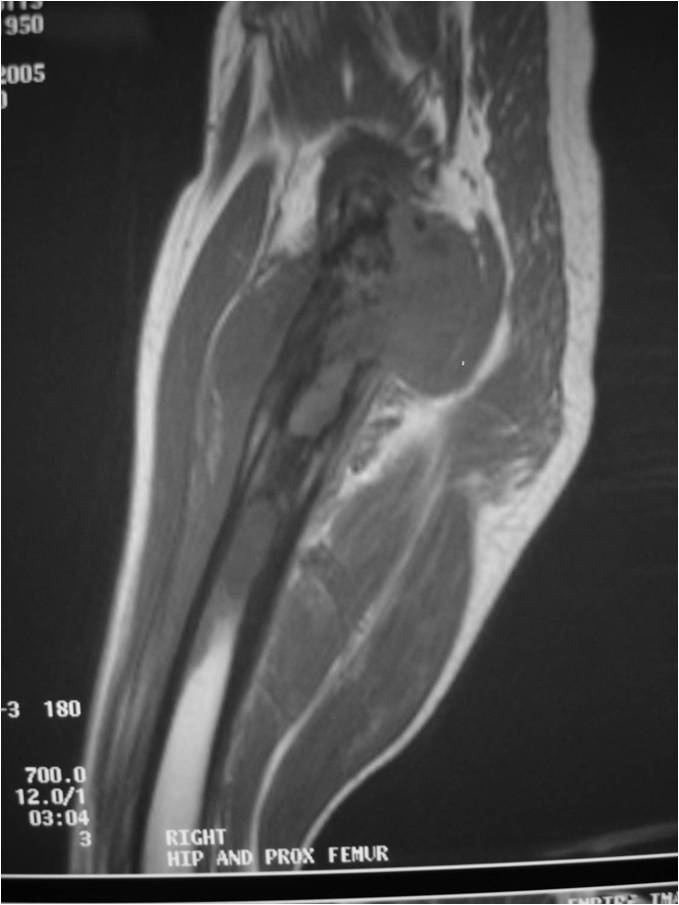

Radiographic Presentation

Radiology emulates pathology: Biphasic Tumor

- One region low grade chondrosarcoma

- Second more aggressive area with bone destruction, lysis of calcification, soft tissue mass

- Cortical permeation and a soft tissue mass in 70% of cases

Ill-defined, lytic intraosseous lesion

- Or extraosseous soft tissue mass

- Devoid of calcifications in continuity with lesions having the features of a cartilaginous tumor

Characteristically abrupt transition between chondroid tumor and dedifferentiated, lytic component

Bone may be expanded and adjacent cortex thickened

(Right Arrow)Aggressive Lytic Area (Dedifferentiated Sarcomatous Component) Cortical Destruction Soft Tissue Mass without Calcification

Biological Behavior

- Very aggressive locally

- Frequently cortical perforation

- Mass is usually large if extraosseous extension occurs